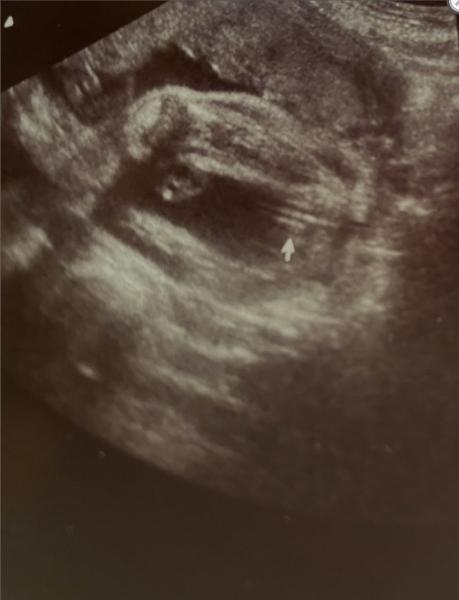

Ich würde tatsächlich sagen, dass es für mich nach einem Babyboy aussieht!  Die meisten verwechseln die drei Linien. Hab mal zwei Bilder im Internet rausgesucht die beide um ca. 20te Woche gewesen sind.  Beim ersten Bild packe ich mal den Jungen rein, beim zweiten das Mädchen. Beide haben drei Linien aber man sieht den kleinen Jungen. Beim Mädchen die Schamlippen Aufteilung.  Bei uns sah es aber echt ungelogen aus wie beim Mädchen. Kann mir bis heute keiner erklären, warum es so war 😄  Aber gut, ab der 25ten woche war aber sofort auf einen Blick zu erkennen was der kleine so zwischen den Beinen hat 😄😄😄